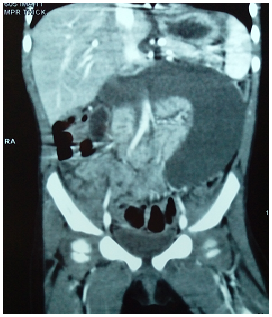

Laboratory investigations revealed low hemoglobin level (Hb=8gm) with mild leukocytosis. Serum electrolytes and coagulation profile were within normal limits. Ultrasound (US) abdomen revealed large intra-peritoneal encysted fluid collection about 8x2x5cm medial to the descending colon with multi-layered wall, turbid content and internal septations. This is associated with multiple mesenteric lymphadenopathy. The mass displaces the descending colon laterally and the small bowel loops, which are seen collapsed, to the right side. CT abdomen with IV and oral contrast revealed a large intra-abdominal cystic lesion about 4x10x10cm abutting aorta, IVC and renal vessels posteriorly denoting a retro-peritoneal origin and displacing the distal duodenum anteriorly and the descending colon postero-lateral. The mass is of inverted C shape with imperceptible wall and turbid content (Figure 1) (Figure 2). Enteric duplication cyst was considered as a main differential and less likely pseudopancreatic cyst. Serum amylase was ordered and revealed to be within normal range.

Figure 1 Coronal CT abdomen revealing inverted C-shape abdominal cystic lesion.

Figure 2 Axial CT abdomen showing imperceptible cyst wall with mildly turbid content.